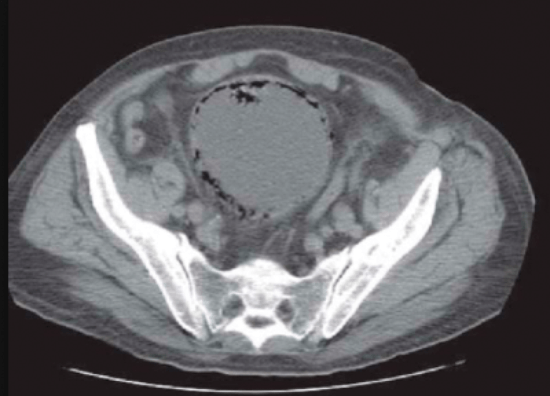

These are a series of radiological images highlighting serious urological infections.

A.

B.

C.

- What are the radiological diagnoses from these images?

Case 3

-

a: emphysematous prostatitis

b: emphysematous cystitis

c: emphysematous pyelonephritis.

Recent instrumentation, fistula from genitourinary tract, trauma, infarctions (spontaneous / elective), urinary diversions, infections.

e.coli, candida, klebsiella, proteus. These organisms can cause sugar fermentation and release of carbon dioxide.

Huang-Tseng CT classification:

Class 1: gas in collecting system

Class 2: gas in parenchyma

Class 3a: extension of gas into perinephric space

Class 3b: extension of gas into pararenal space

Class 4: Bilateral or solitary kidney.